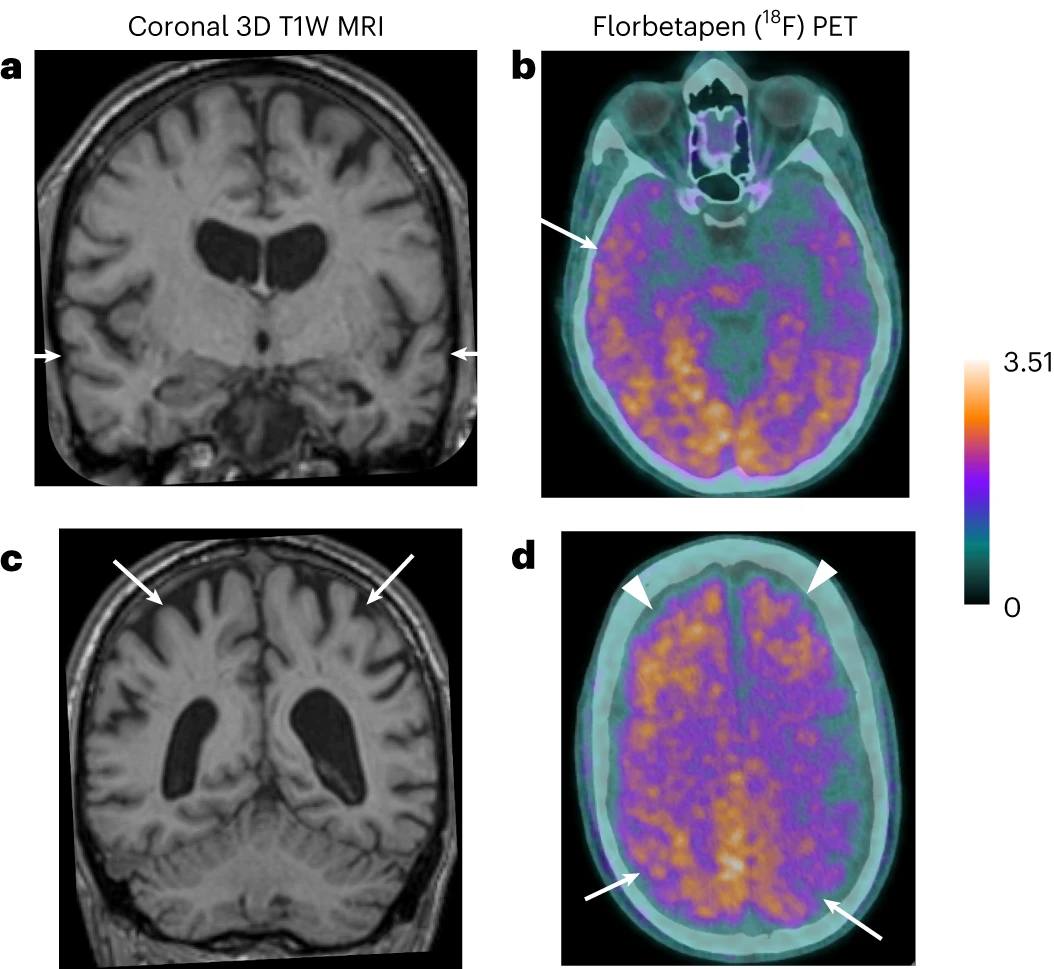

На благо человечества: Последствия не используемого сейчас метода гормональной терапии позволили учёным глубже понять причины болезни Альцгеймера.

🔹 Исследователи из Института прионных заболеваний Университетского колледжа в Лондоне впервые описали случаи заражения людей болезнью Альцгеймера при использовании препаратов человеческих белков. Речь идёт об инъекциях гормона роста, выделенных из из трупных тканей человека (не применяется с 1985 года). Учёные обнаружили 8 человек из почти двух тысяч прошедших данное лечение в детстве, у которых в итоге развилась болезнь Альцгеймера, и убедительно доказали её возникновение в результате медицинского вмешательства